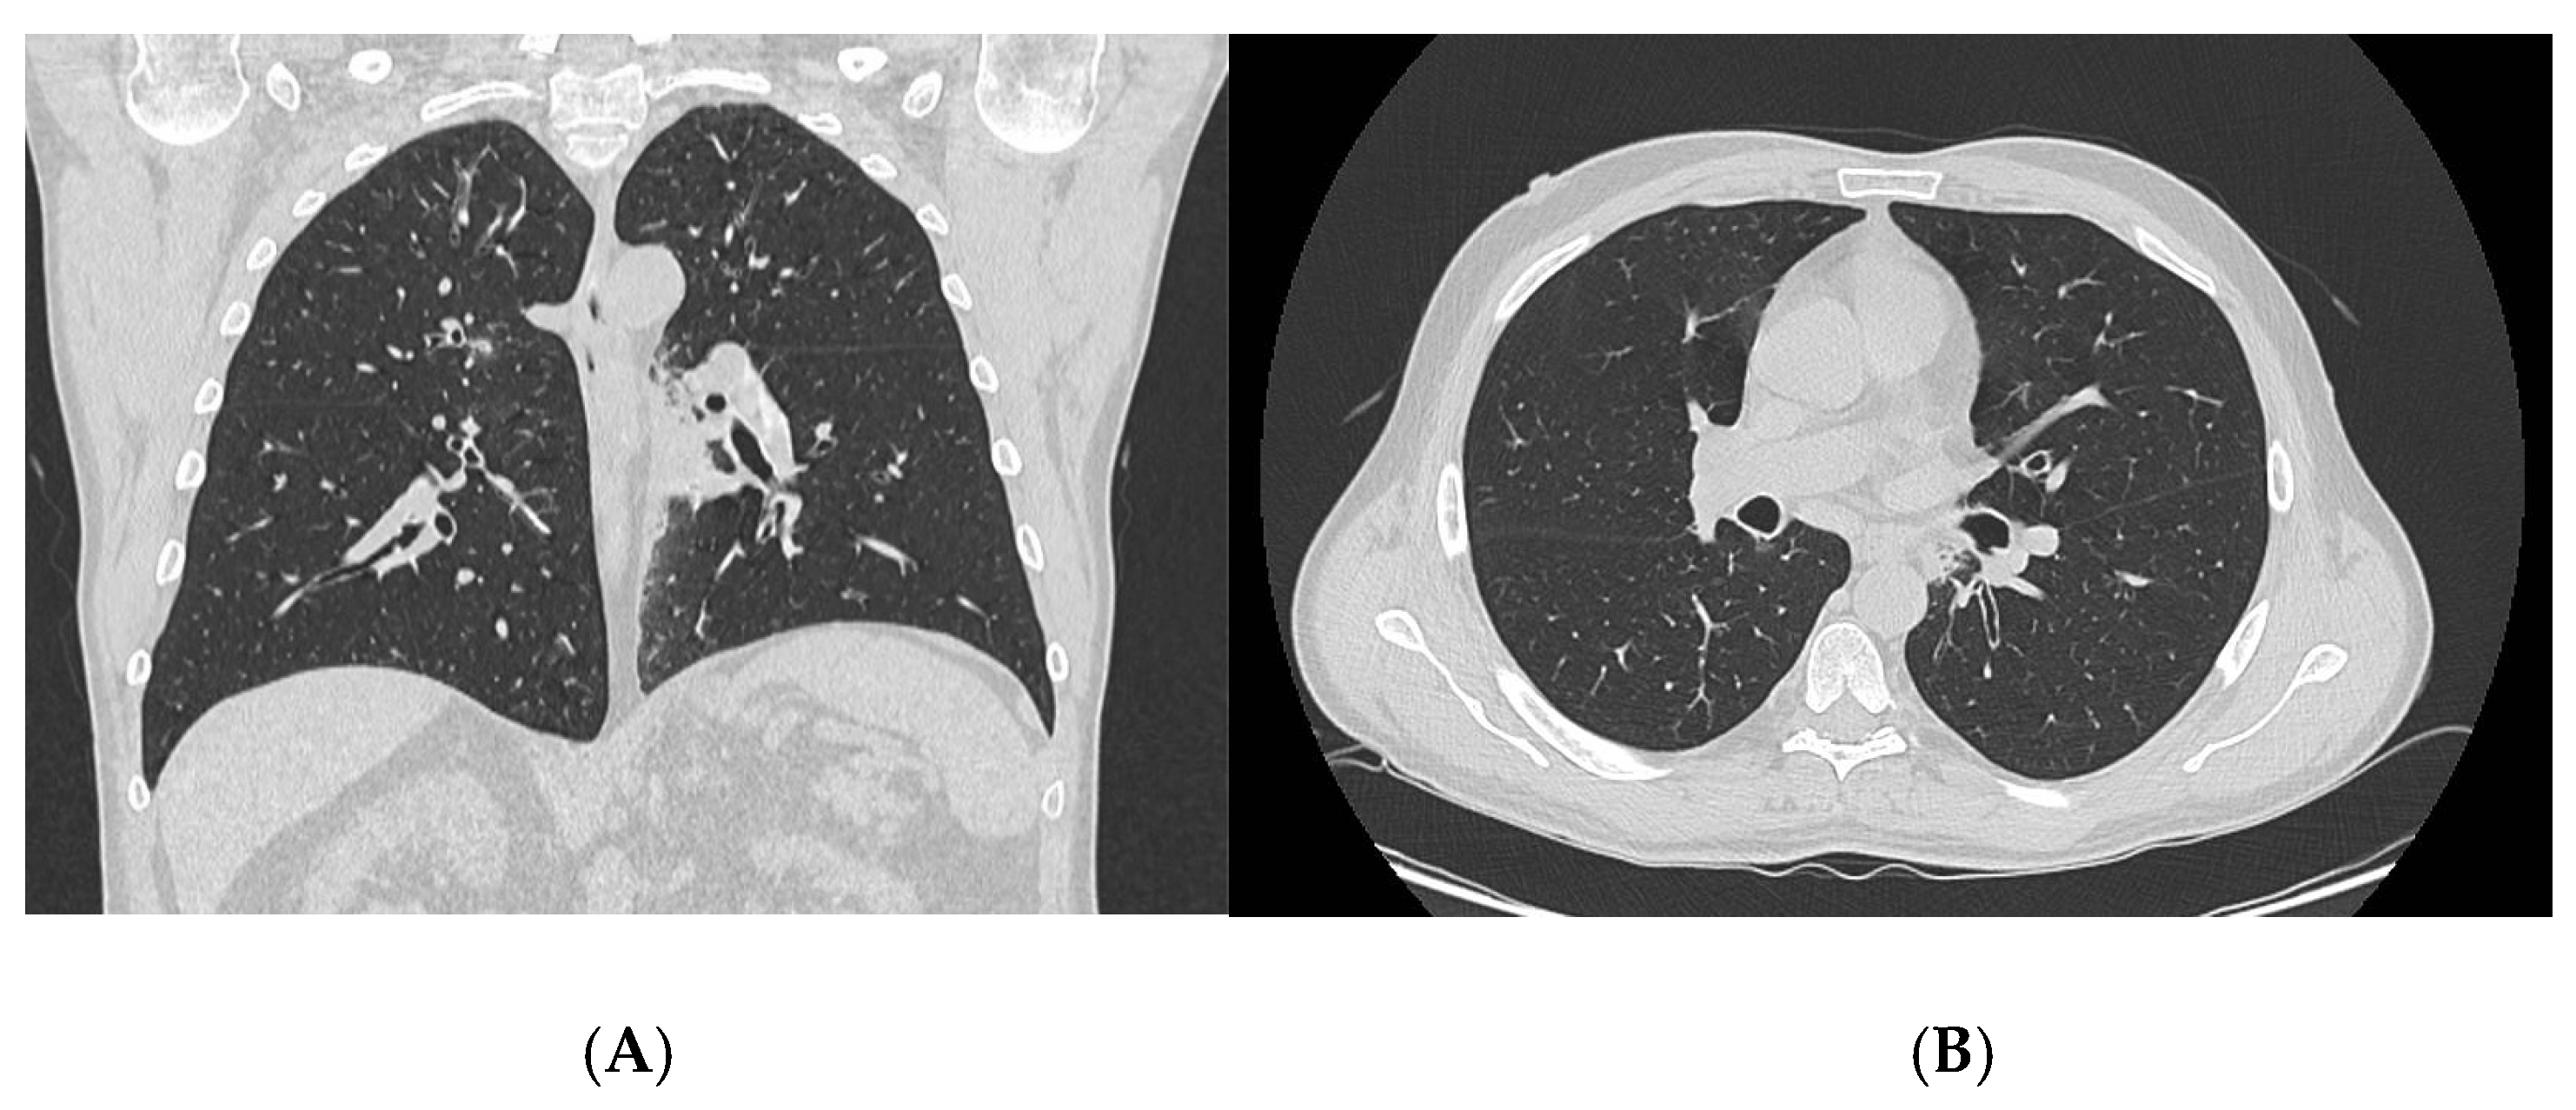

3.1. Case N. #1

| 23. Our patient #1 | 67 | M | Asthma, CRwNP, recurrent otitis media | NA | Inhaled CS/LABA OCS | General symptoms, gastroenteritis, otitis complicated by bilateral otomastoiditis, bilateral lung consolidations and pleural effusion | AEC: 5630/μL CRP: 117 mg/L MPO-ANCA: - | 2 | Yes | IV steroid therapy followed by OCS (50 mg/d) Mepolizumab (300 mg/4w) |